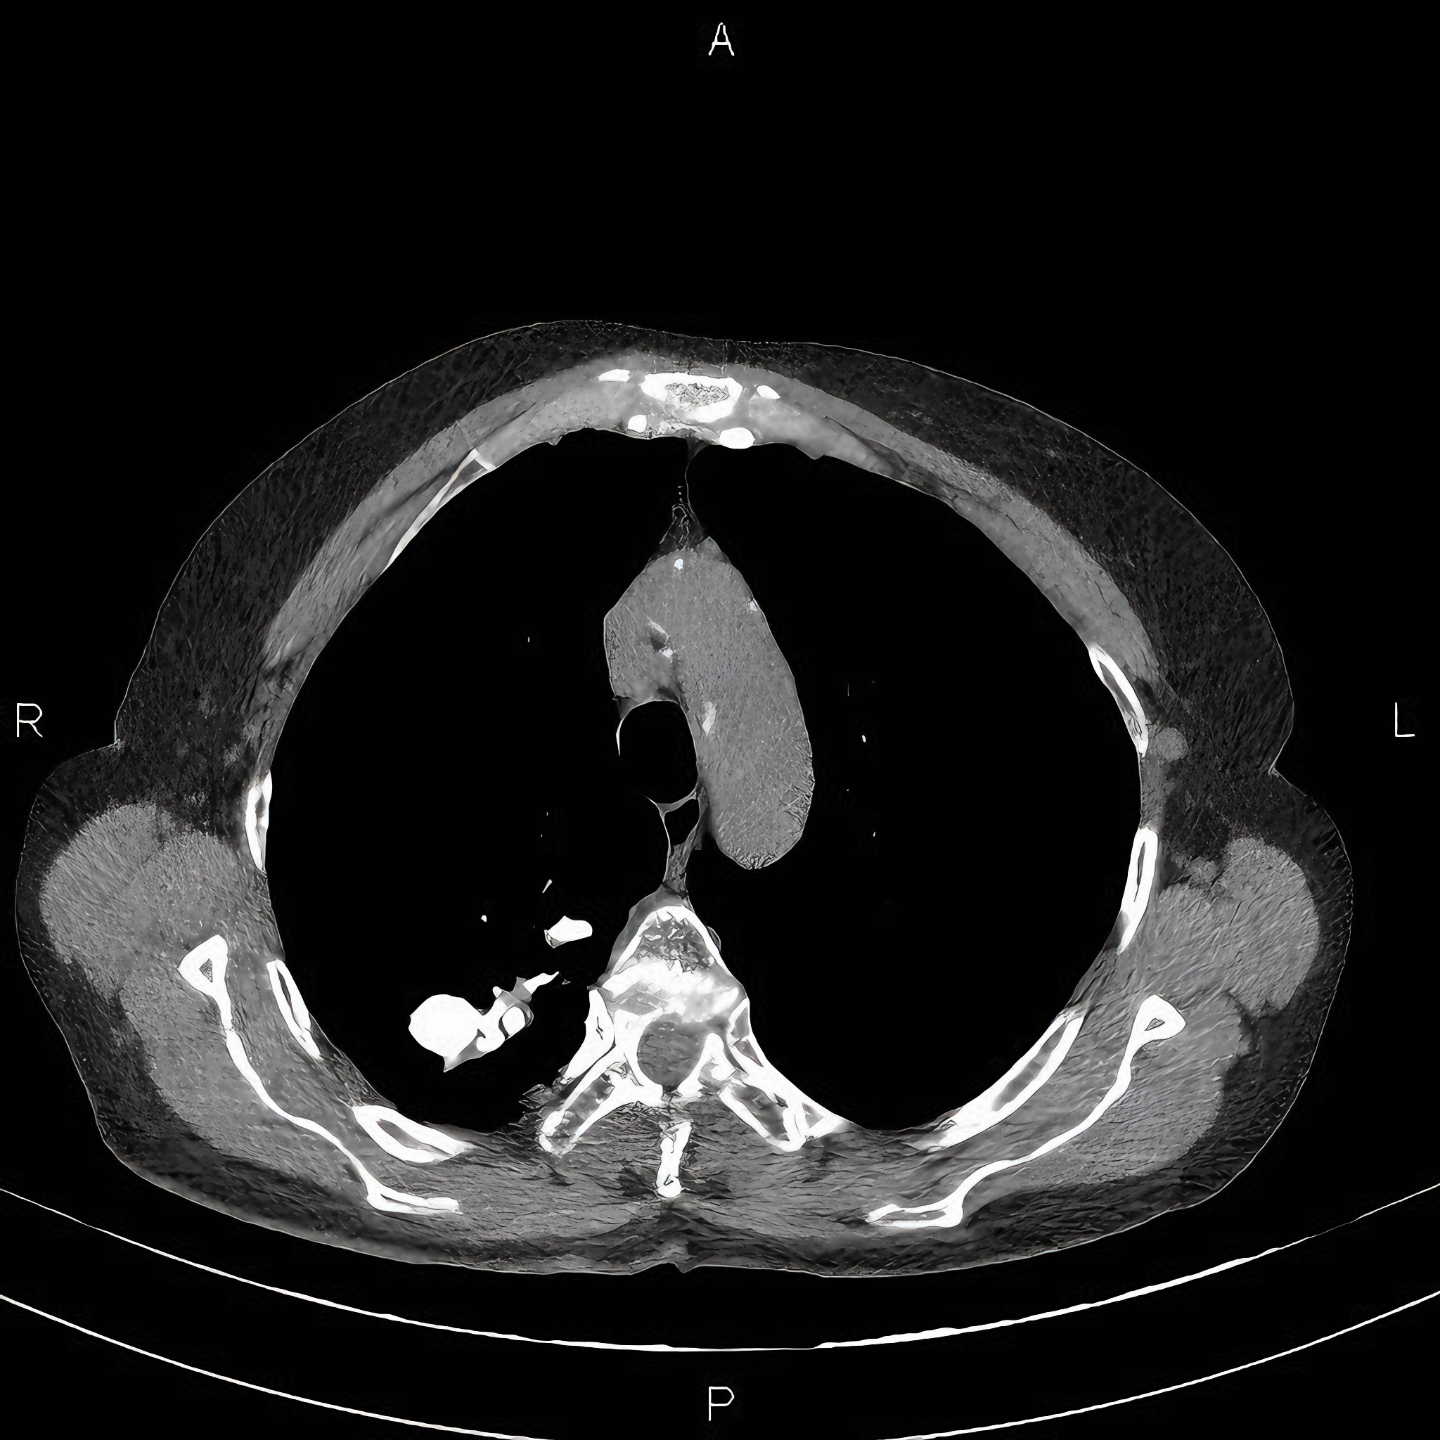

마왕퇴 귀부인에게서는 왼쪽 허파 위쪽에에서 "결핵성 경화병소"가 있었다고 하였는데,

아마도 결핵 때문에 오는 석회결절을 확인한 것일 터다.

결핵을 앓다가 오랜 시간이 지나면 그 자리에 석회 결절이 만들어진다.

이것은 방사선 사진을 촬영하면 하얗게 흔적이 나타난다.